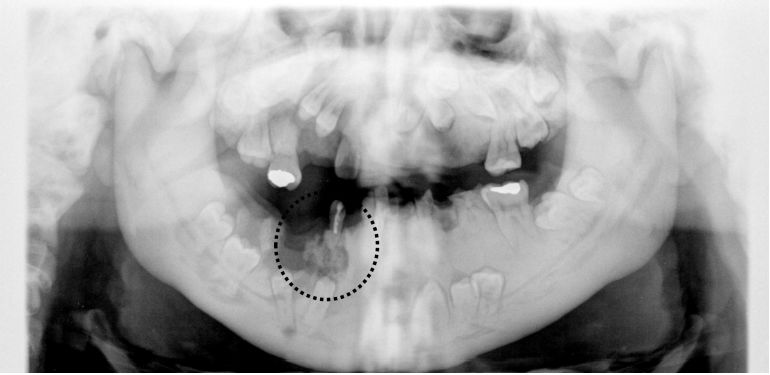

75.一名15歲男孩因下顎右側犬齒附近疼痛而來求診,經X光檢查如附圖所示,發現病患的上下顎骨密度不正 常,其最有可能罹患何疾病?(A)變形性骨炎(osteitis deformans)(B)骨發生不全(osteogenesis imperfecta)(C)骨質石化症(osteopetrosis)(D)骨質疏鬆症(osteoporosis)

76.承上題,此病患之下顎右側犬齒附近疼痛區如附圖黑圈區域所示,下列何者為最可能之診斷? (A)牙骨質骨化發育異常(cemento-osseous dysplasia) (B)慢性骨髓炎(chronic osteomyelitis) (C)纖維發育不良(fibrous dysplasia) (D)增殖性骨膜炎(proliferative periostitis)